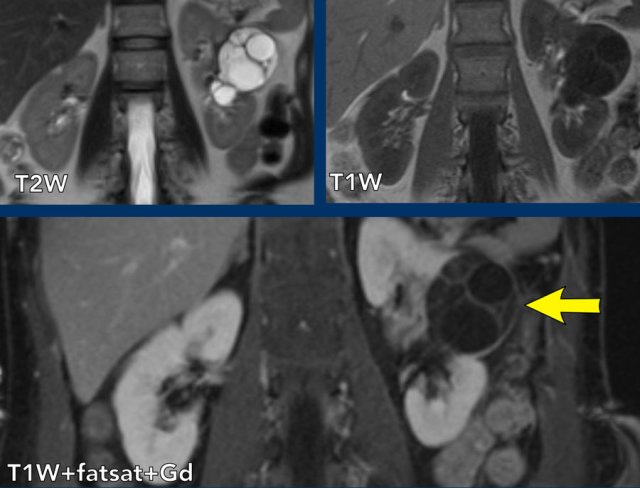

case 1

The images show a complex large right renal cyst with T1 and T2 hyperintense internal fluid and T1 hyperintense debris, which shows mild enhancement on the subtraction image.

This cyst also has an enhancing mural nodule (see arrow coronal images), classifying it as a Bosniak IV lesion.

The kidney was removed and the cyst represented a papillary renal cell carcinoma